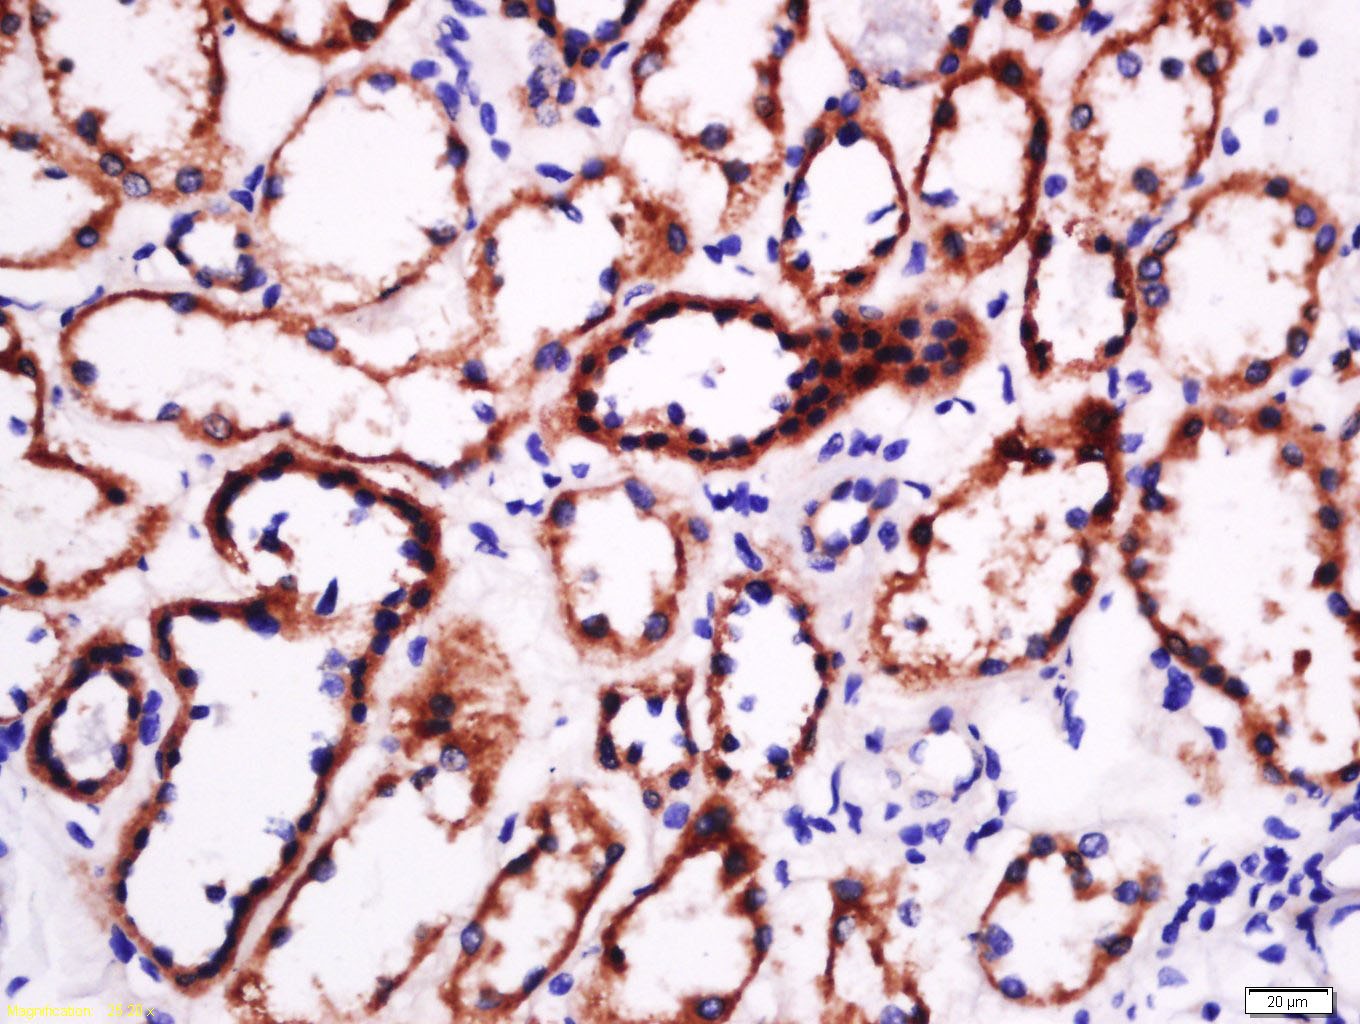

2. Tissue/cell: human kidney tissue; 4% Paraformaldehyde-fixed and paraffin-embedded;

Antigen retrieval: citrate buffer (0.01M, pH6.0), Boiling bathing for 15 min; Block endogenous peroxidase by 3% Hydrogen peroxide for 30 min; Blocking buffer (normal goat serum) at 37°C for 20 min;

Incubation: Anti-laminin Polyclonal Antibody, Unconjugated (TMAB-01044) 1:500, overnight at 4°C, followed by conjugation to the secondary antibody and DAb staining.